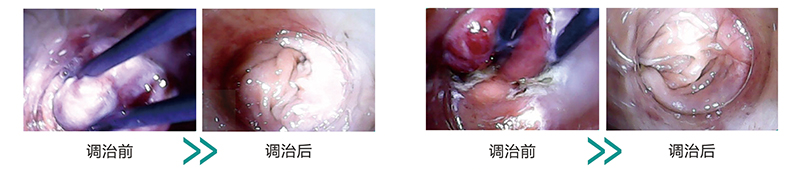

痔疮电解治疗法是在祖国医学枯痔钉疗法的理论体系和微电流电化学法理论的基础上加以改进、研发的一项无需麻醉无痛无创调治内痔及混合痔的一种特色理疗方法。适用于湿热下注、气滞血淤、脾虚气陷、阴虚肠燥型等人群,通过智能微电流理疗设备,连接配套特制痔漏探针在微电流电场的作用下,快速导致痔血管团闭塞,至到痔体萎缩、制止出血的效果,这种无痛无创无需麻醉的特色理疗法,真正实现了“无创断痔”的无痛新理念

案例展示: